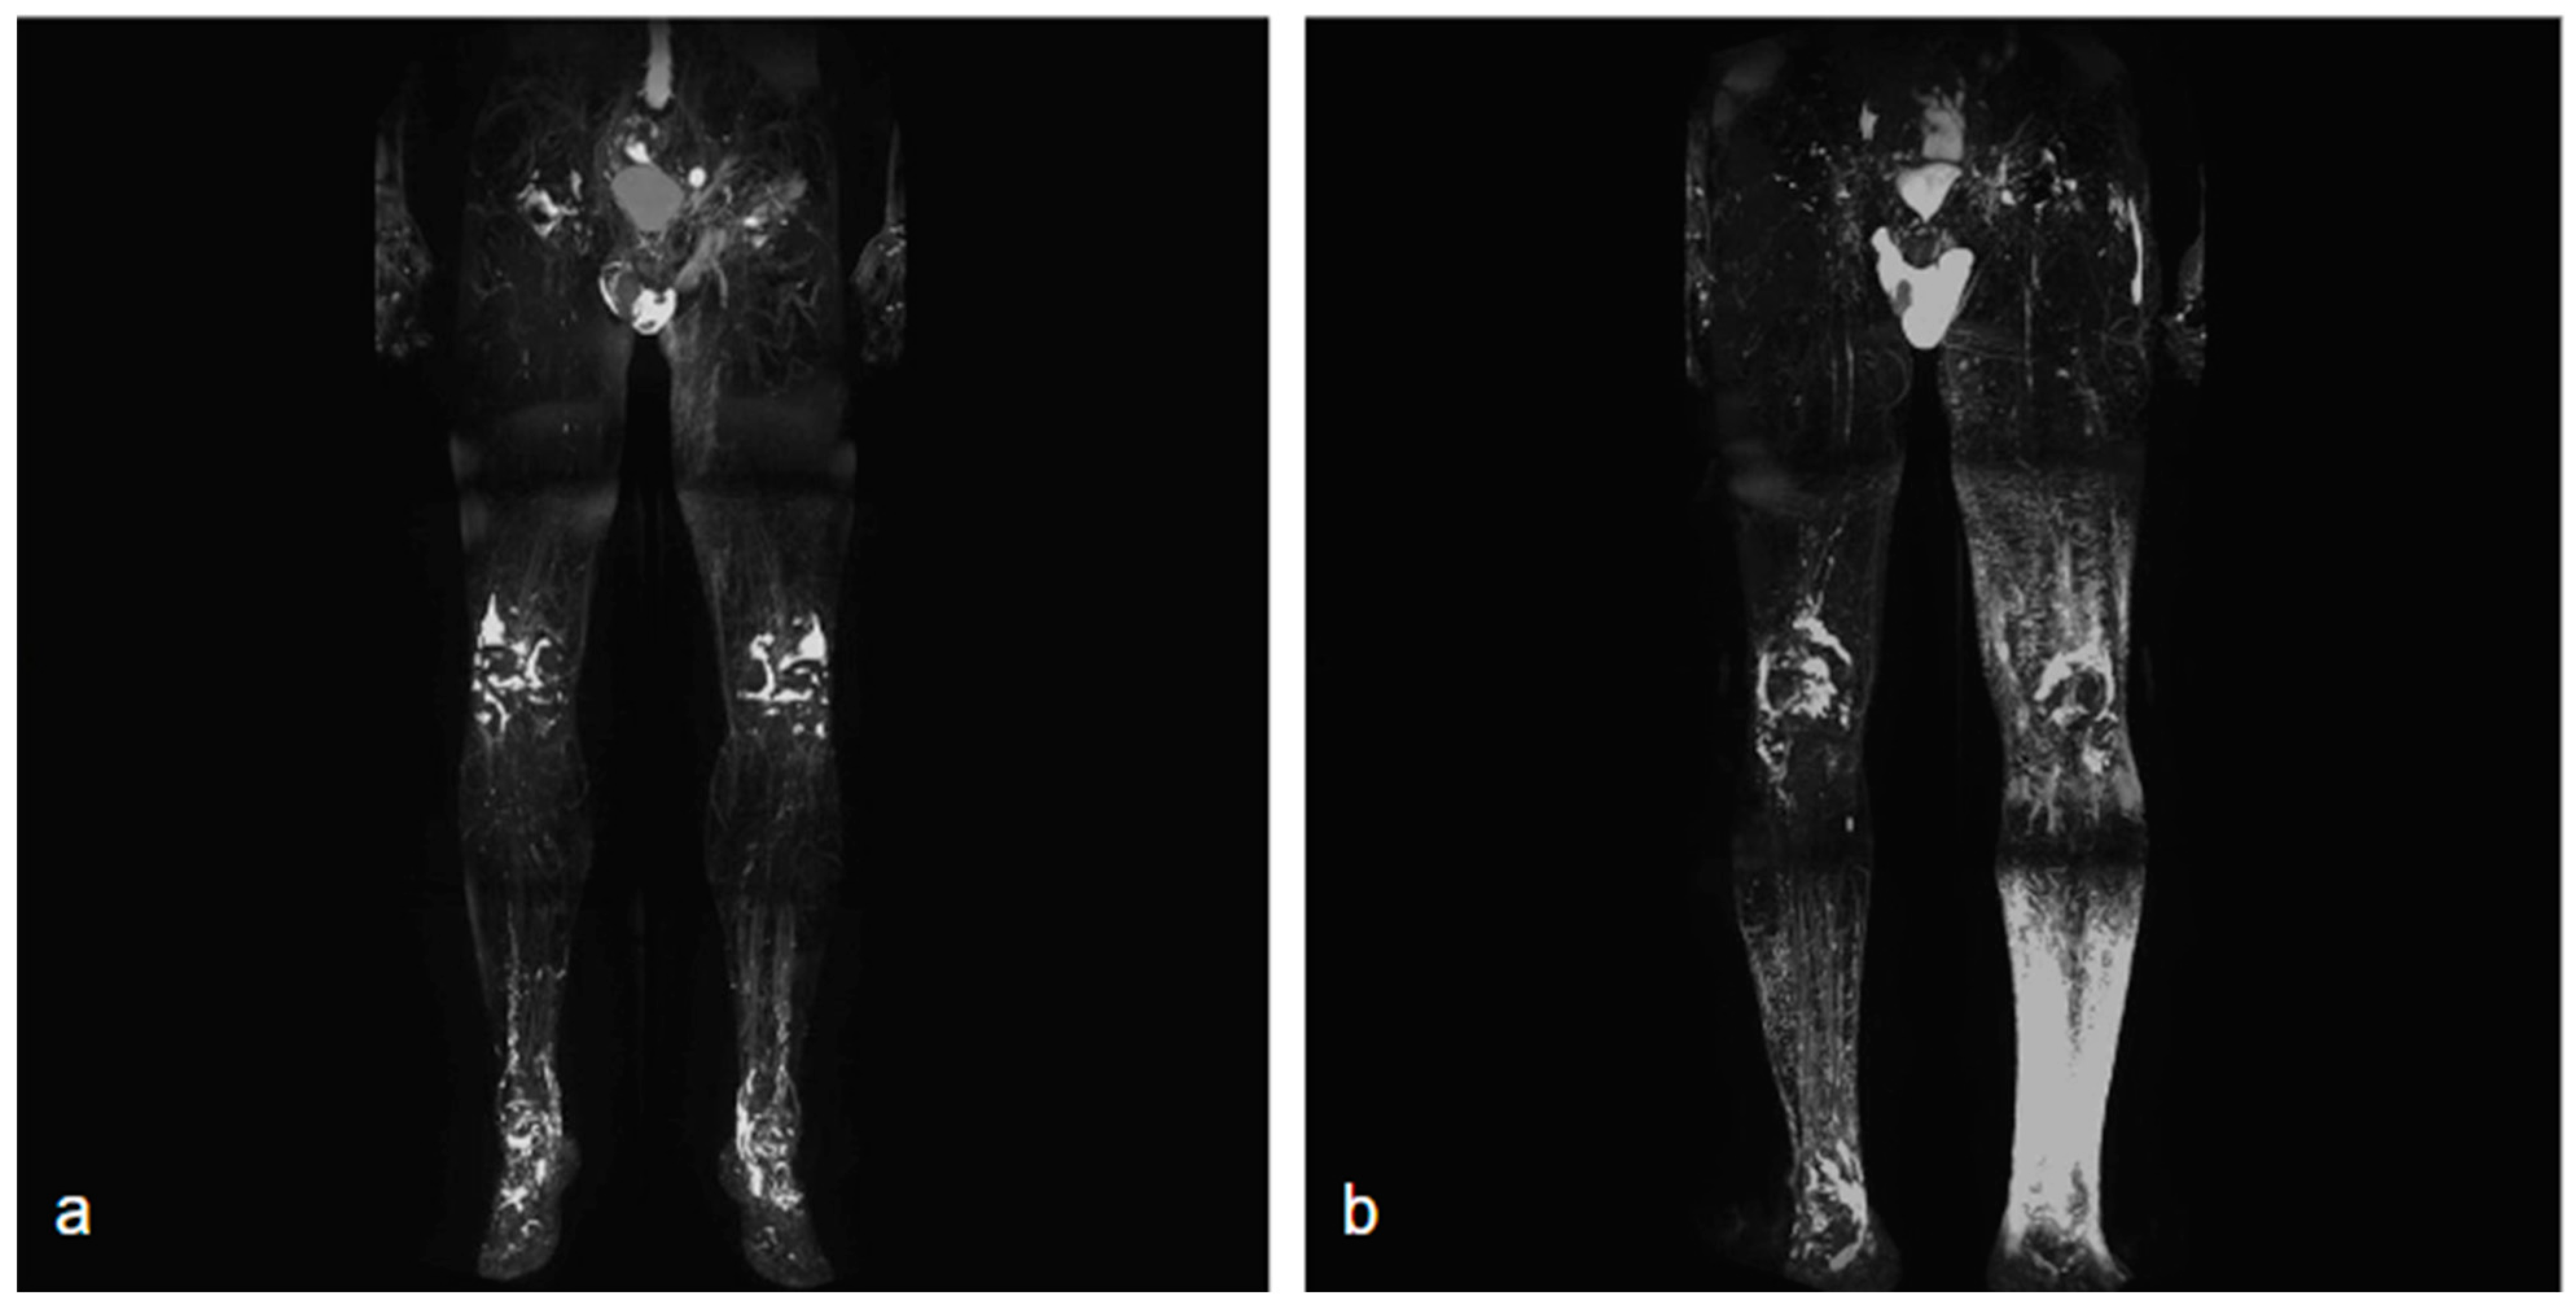

NCMRL protocols are still evolving, but the base of this examination consists of heavily T2-weighted sequences, with very long both Repetition Time (TR) and Echo Time (TE), usually performing 3D sequences (to create rotating 360° 3D post-processed images and maximum intensity projection (MIP) reconstructions), with very long TR/TE ratio to assess the extent and distribution of the lymphedema [34] (Figure 1).

Figure 1.

Two different NCMRL. On the left (a), a patient with mild post-prostatectomy lymphedema with a left iliac lymphocele associated. On the right (b), mild–severe lymphedema is more represented in the left limb, with scrotal localization.